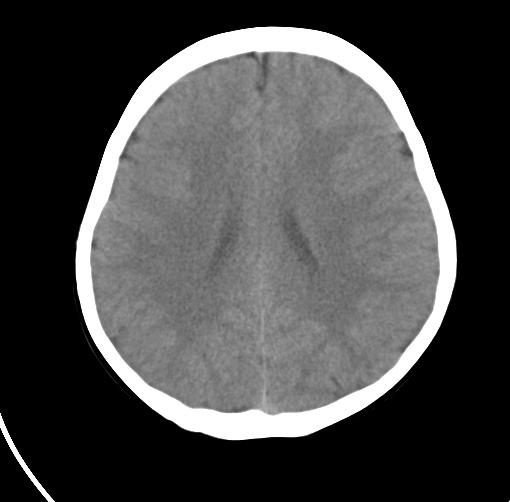

以下是引用sunjh2266在2007-7-31 23:35:00的发言:[br]脉络膜裂,是胚胎发育过程中脉络襞突入侧脑室下角构成脉络丛时形成,位于丘脑下部与海马之间,走行与海马平行。脉络裂内侧通于环池,外侧为侧脑室下角,前面是海马钩及杏仁体,后部与海马沟交通。脉络裂内有参与组成侧脑室脉络丛的脉络膜前动脉及脉络膜后外动脉及其分支走行。[br] mri轴位像,在大脑脚的前外侧多能显示脉络裂的前部,呈左右走行的含脑脊液间隙,前后内外分别与杏仁体、海马、海马钩及侧脑室下角相邻(图1);冠状位像,在扫及脑干的多个层面上,脉络裂均可被清晰显示,因而是显示脉络裂的最佳扫描方式。偏前的部分层面还可见到呈切迹状的海马沟走行于海马旁回内上方;矢状位像,海马旁回上方可见一分叉状裂隙,类似一斜卧的“入”字,接近水平走行的一撇为脉络裂,而由后上向前下走行的一捺为从扣带沟延续而来的海马沟。[br] [br]